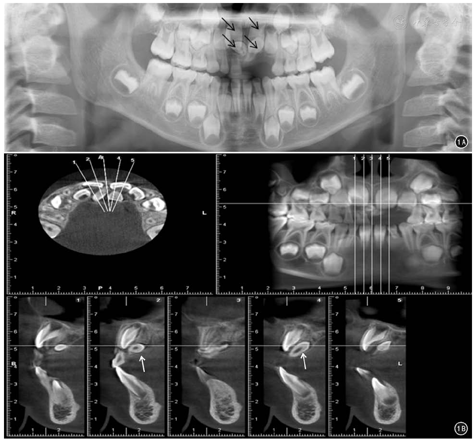

典型病例:患儿男,7岁,因"上前牙未萌出1年"入院。口腔全景片检查示上颌中切牙对应颌骨内有4个牙样的阻射影像(图1A),CBCT检查发现双侧上颌中切牙腭侧有2颗多生牙均未萌出(图1B)。全身麻醉下行上颌埋伏多生牙摘除术+上颌骨皮质骨开窗术。CBCT显示多生牙表面有部分正常骨质,术中所见与术前CBCT显示一致。术中以磨头磨除骨皮质,顺利拔除埋伏多生牙。

CBCT检查弥补了全景片不能准确定位的缺点。CBCT属于数字容积体层摄影,能够显示埋伏多生牙在颌骨内三维影像[6,7];采用平板探测器技术,扫描范围包括上、下颌骨,切片最薄为0.2 mm;对埋伏多生牙进行矢状面、冠状面及横断面层的观察,并建立牙齿的三维外形[8];能较好地显示病变组织和正常组织结构,避免了二维影像学检查固有的缺陷[5]。但是,临床中会遇到有的上颌前部埋伏多生牙远离牙弓的情况,此时CBCT不能很好地反应真实情况,就需要口腔全景片做补充。本组有1例患儿颌骨内存在2颗多生牙,但CBCT显示只有1颗,全景片则显示了全部2颗,本组51例患儿术前口腔全景片联合CBCT对埋伏多生牙的诊断及定位准确率为100%。